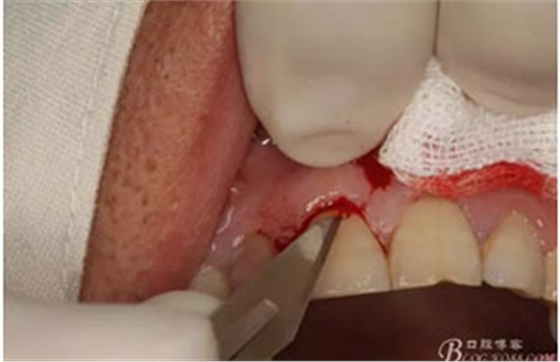

圖6.行唇側(cè)角形切口(11近中垂直切口+齦溝內(nèi)水平切口)垂直切口距離前庭溝約1~2mm。這樣可以減輕術(shù)后腫脹。

圖7. 角形切口中的齦溝內(nèi)切口情況:11號刀片伸進(jìn)齦溝內(nèi)斜切。